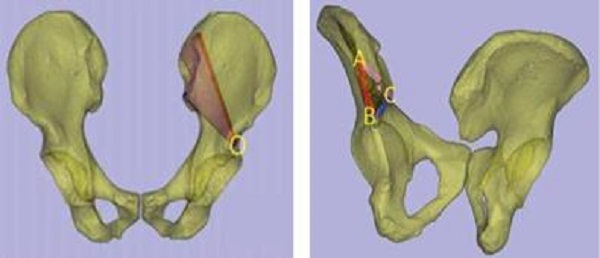

术前,创伤骨科郭永良主任医师团队应用MIMICS软件重建患者骨盆LC—II通道螺钉方向和长度,术中郭永良主任亲自主刀,使用Schanz针协助闭合复位,结合术前模拟通道螺钉方向精确制导,以最小的创伤将LC-Ⅱ通道螺钉顺利置入合适位置,而且完美避开神经及血管损伤,仅通过3枚螺钉使骨盆LC—II型骨折得到有效的稳定固定。

软件重建通道螺钉位置: